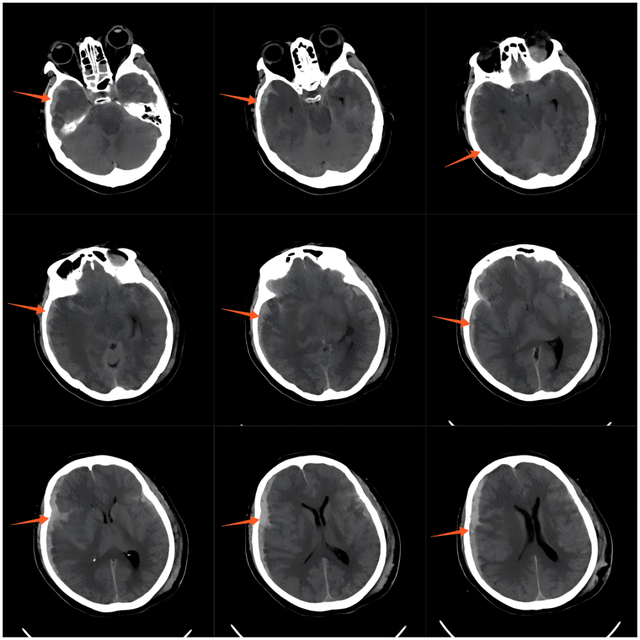

▲急诊术前CT影像

68岁的张女士(化名)

因严重车祸导致颅内出血及全身多发伤

急诊行开颅血肿清除术后

生命体征虽稳定

却陷入微小意识状态-(MCS-)

术后3个月

其意识水平仍停滞GCS:5T(M3VTE2)

仅能通过疼痛刺激短暂睁眼

但无法言语交流,生活完全依赖护理